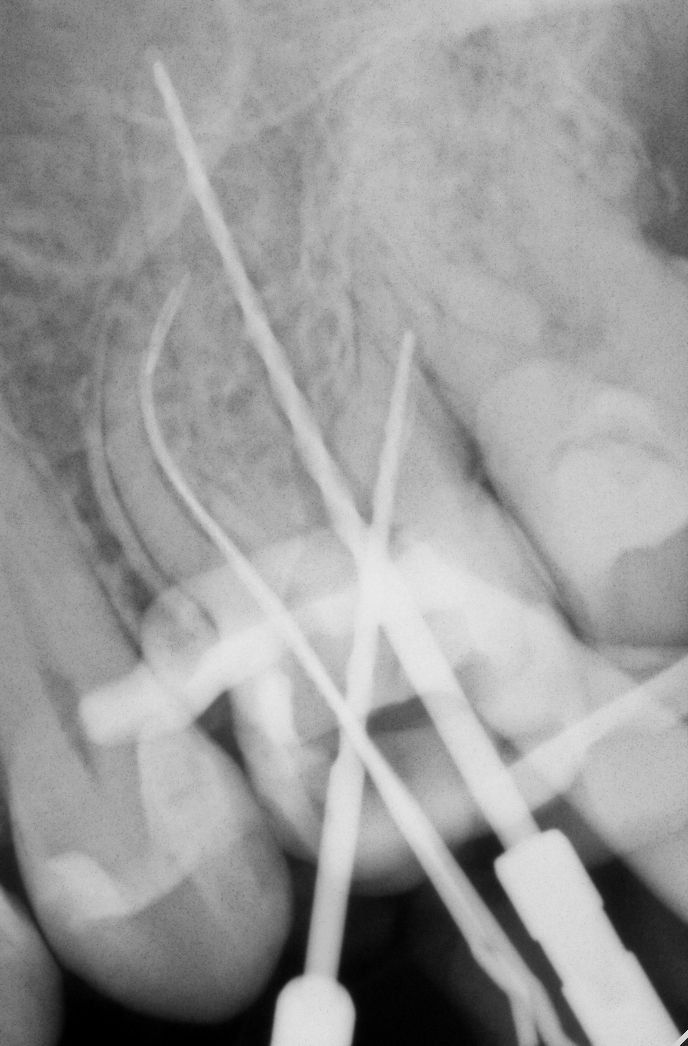

Первое, что нужно сделать — попробовать байпас. Если вы работаете с бинокулярами, можно пробовать байпас даже когда обломок застрял в средней трети. если обломок тонкий или каналы сходятся, в канале практически всегда найдётся пространство, чтобы его обойти. И это гораздо безопаснее для зуба, чем сразу хвататься за ультразвуковую насадку.

Байпас не удался, а периапикальный очаг присутствует. Здесь нужно оценить: можно ли безопасно извлечь обломок? Ультразвук? Апикальная хирургия? Если да — извлекаем. Если нет — обломок лучше оставить. Потому что даже при наличии очага и оставленного фрагмента уровень заживления составляет порядка 80%. А вот агрессивное извлечение может значительно ухудшить реставрационный прогноз зуба.